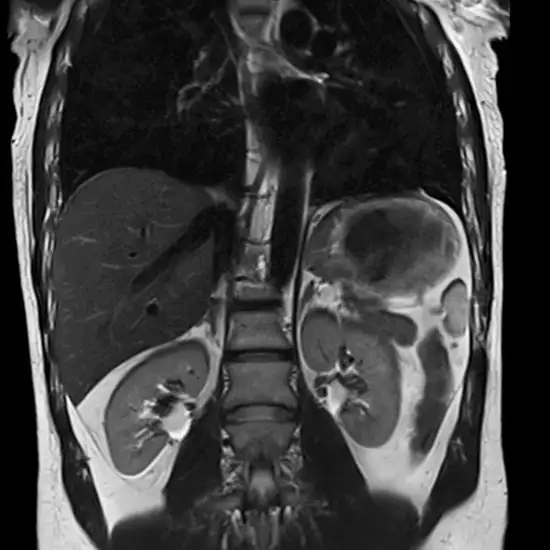

Request A Call Back